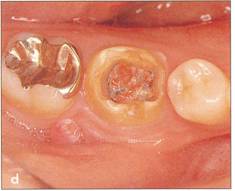

Fi 545e45f g 5-1e Preoperative view of the donor tooth and the recipient site. |

|